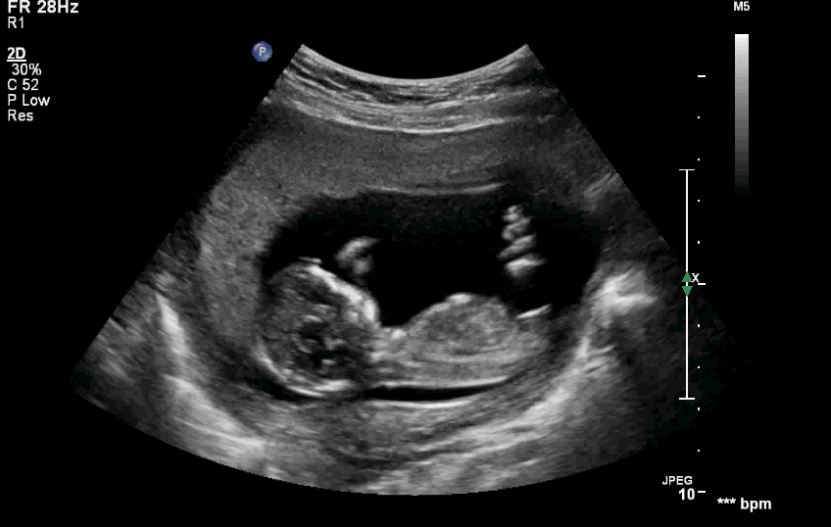

Hi there, below are some nub images from our 13 week scan. Would greatly appreciate your guesses of the baby's sex? I can't make up my mind.